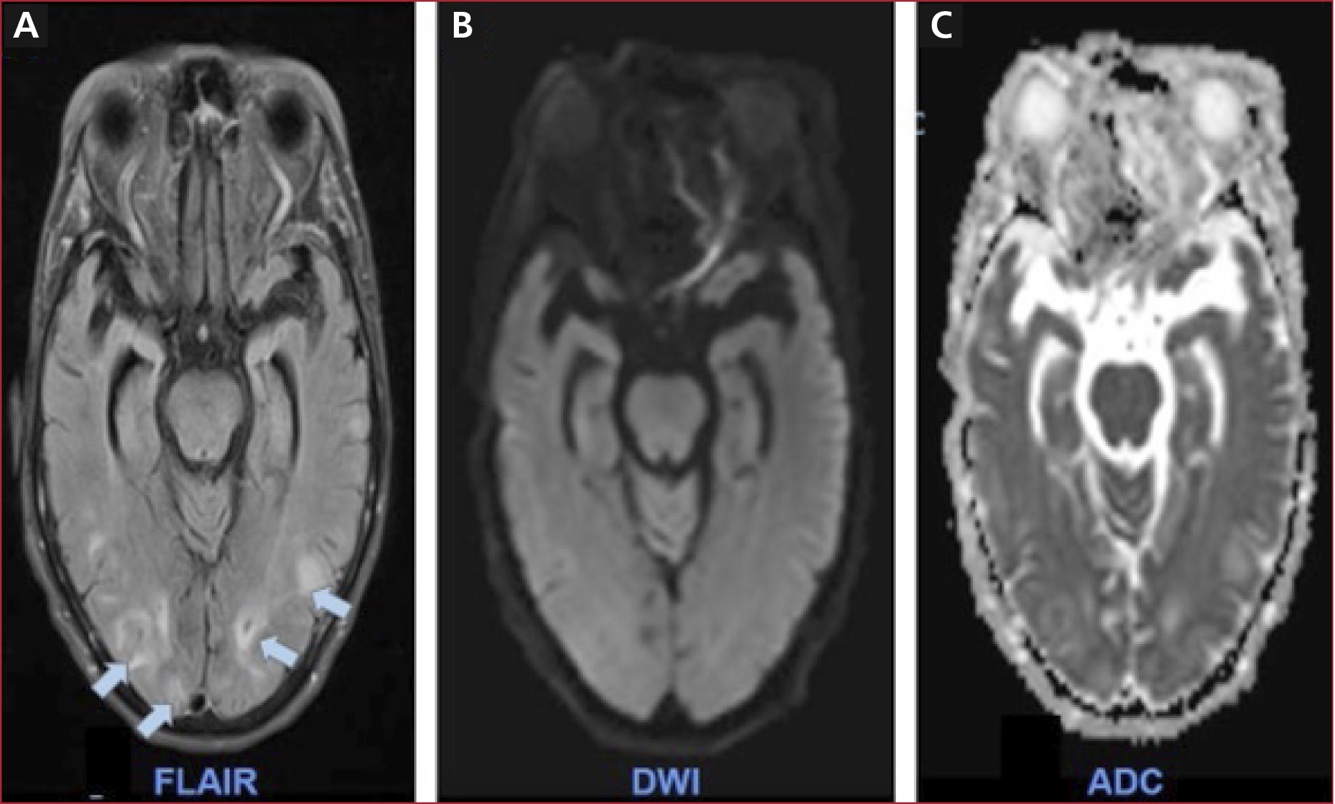

Mujer de 69 años, con antecedentes de hipertensión arterial e

hipotiroidismo. Consultó por un cuadro neurológico agudo caracterizado por

mirada fija, mutismo y hemiparesia braquiocrural

derecha. Al ingresar, tenía una presión arterial de 210/110 mmHg

y la tomografía computarizada de cráneo simple era normal. En la resonancia

magnética cerebral en secuencia FLAIR, se observaron múltiples

hiperintensidades cortical-subcorticales de predominio occipital (Figura,

flechas azules), sin restricción en las secuencias de difusión (DWI) ni en el

mapa ADC (Figura), hallazgos compatibles con un síndrome de encefalopatía

posterior reversible (posterior reversible encephalopathy

syndrome, PRES. El principal diagnóstico diferencial

es el accidente cerebrovascular de circulación posterior, que se descarta por

la ausencia de restricción en las secuencias de difusión.

Figura. Resonancia magnética cerebral. A. Secuencia FLAIR. Se observan múltiples zonas

de hiperintensidad de predominio cortical-subcortical en lóbulo occipital

(flechas azules). B y C. Secuencias DWI y ADC, respectivamente, sin

restricción en las secuencias de difusión, por lo que se descarta una isquemia

aguda.